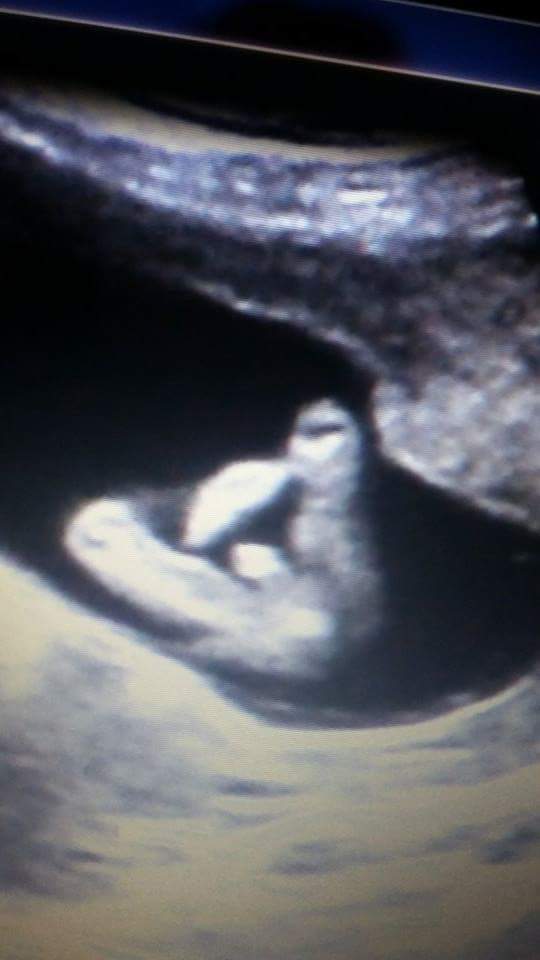

Hi! Can you help me ? I have two pictures. One that shows nub and the other potty shot. Our doctor gave us a guess (boy 70%) but she wasnt sure if it was the cord between the legs or not.

Boy :DS:

Boy :)

Boy

Boy xx